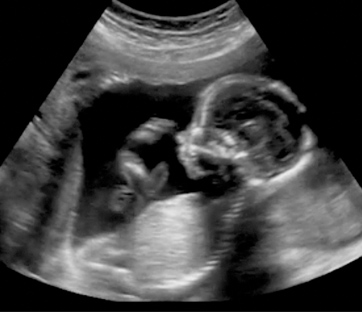

I dati parlano da sé. Secondo il rapporto CeDap del ministero della salute, in Italia nel 2010 il 73% delle donne in gravidanza ha effettuato più di tre ecografie e l’85% più di quattro visite ostetriche. Solo il 3% delle donne effettua la prima visita dopo la dodicesima settimana, percentuale che sale al 14% delle madri straniere. L’indagine mette in evidenza inoltre l’eccessivo ricorso al parto cesareo che si effettua nel 37% delle circostanze, anche in questo caso con una netta differenza tra madri italiane e straniere (il 38% contro il 29%). Una tendenza, il ricorso al cesareo, che ha registrato un aumento un po’ in tutta Europa.

Per questa ragione la medicina, tenuto conto anche degli insuccessi, è chiamata a investire in ricerca e trovare soluzioni nuove. “Personalmente sono per una procreazione consapevole e informata”. La pratica ostetrica, che non è solo pubblica ma anche privata, deve farsi interprete della volontà dei genitori, i quali con un “atto di grande responsabilità” vogliono accertarsi della salute del proprio figlio prima della nascita. Perché oggi il paziente partecipa in modo consapevole alla cura medica.

“Non nego che a volte ci sia un accanimento terapeutico legato a un virtuosismo medico che, in alcuni casi, dovrebbe invece prendere atto dell’impotenza della medicina. Ma non si deve trascurare che gli esami clinici in alcuni casi rappresentano un vero e proprio ‘salvavita’. Durante la gravidanza, ad esempio, riuscire a diagnosticare una cardiopatia congenita prima della nascita permette di programmare un intervento mirato”.